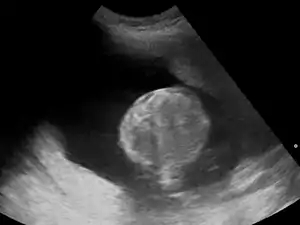

- sacrococcygeal teratoma